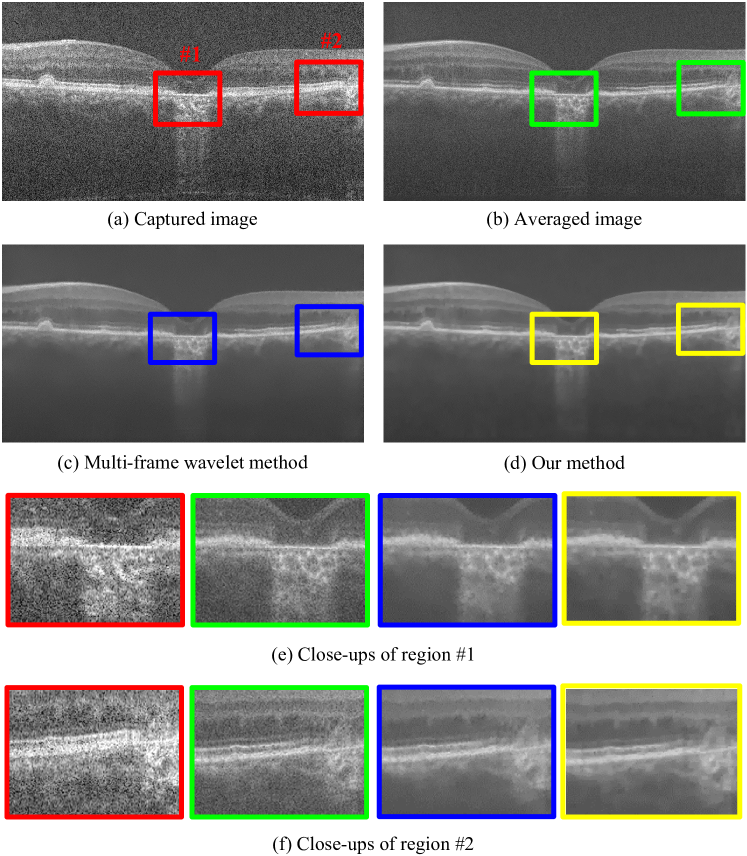

To further test the practical denoising effectiveness of our method, we conduct a denoising experiment on human retinal OCT images. We use the same public dataset as that used in [45], which is acquired by a SDOCT imaging system from Bioptigen Inc. with similar-to\sim4.5μ𝜇\mum axial resolution, 500 A-scans per B-scan and 5 azimuthally repeated B-scans in each volume. Similar to the processing progress described in Sec. 2.1, we firstly register the OCT frames and then use different methods to denoise these frames. Considering that the anisotropic diffusion method, the Bayesian method and NSC leave too much noise on the recovered images, and thus own little competitiveness compared to the other two multi-frame methods, here we only present the denoising results of the multi-frame wavelet method and our method for clearer comparison.

Fig. 4: Denoising results of the human retinal OCT images. Input: 5 frames of the human retina data. (a) shows one of the 5 captured frames, and (b) is the average of the 5 frames. (c) and (d) are respectively the results of the multi-frame wavelet method and our method. Close-ups of two selected regions of interest are shown in (e) and (f), which offer a clearer comparison.

The results are shown in Fig. 4, which exhibits similar performance ranking to that of the pigeye data. Comparing the denoising results produced by the multi-frame wavelet method and our proposed method carefully, we can see that the result of the wavelet method contains undesired edge burrs, while our result presents clearer layer boundaries (such as the horizontal layer edges in the two selected regions), which would help a lot in follow-up analysis of the denoised images, such as OCT layer segmentation and diagnosis.